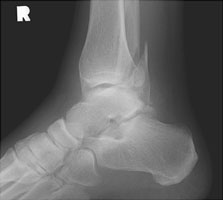

Weber C Fracture |

The Weber classification is used to determine the severity of tibiofibular ligament injury by the level of fibular fracture. The Weber C fracture consists of a proximal fracture of the fibula and a transverse fracture of the medial malleolus (or an intact malleolus and a ruptured deltoid ligament). This results in complete disruption of the tibiofibular ligament complex and is from pronation-lateral rotation injury.